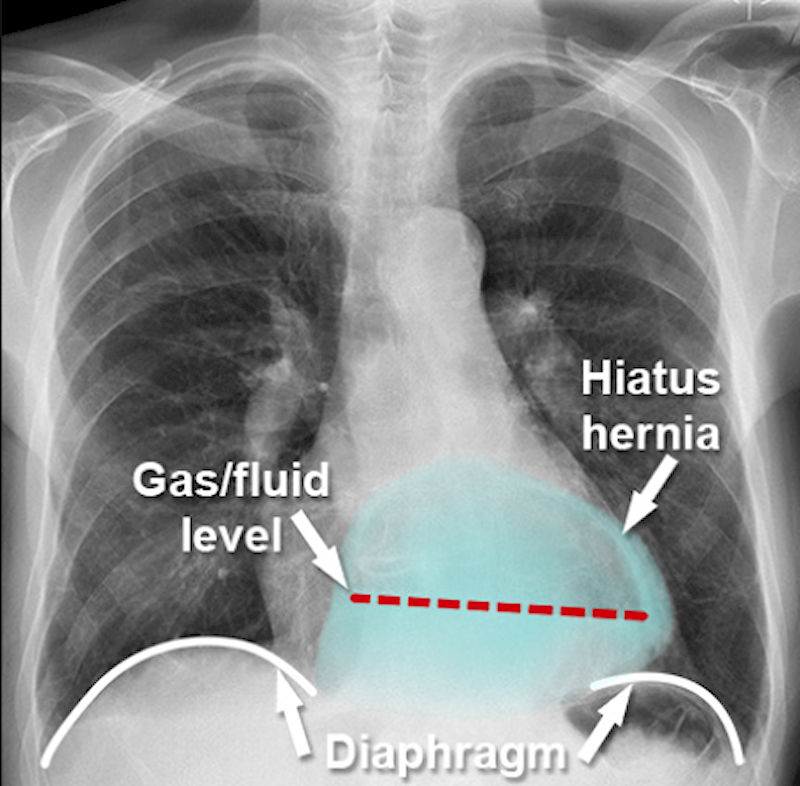

Рентген с контрастом (барием) — рентген грудной клетки использует для получения чёрно-белых изображений внутренней части грудной полости, где расположен пищевод чтобы определить размер и тип ГПОД.